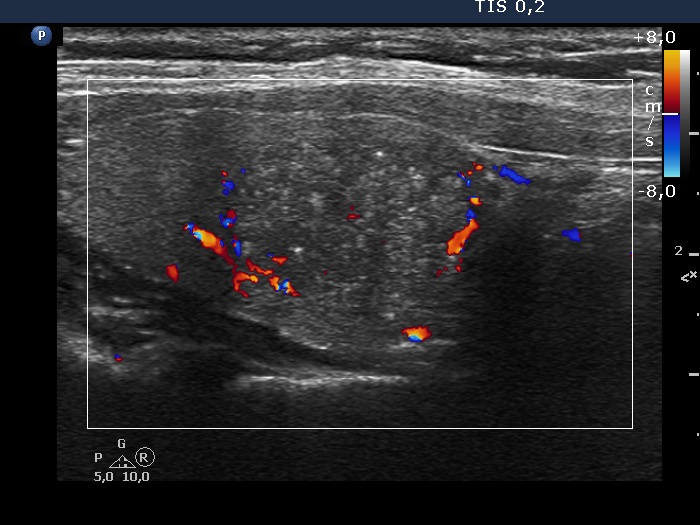

Ultrasonography. The thyroid was echonormal. There was a hypoechogenic nodule in the right lobe. The nodule had numerous punctate echogenic granules.

The echogenic figures are very difficult not to interpret as microcalcifications. Nevertheless, thorough analysis reveals that some of the bright granules has a short tale, and great proportion of these figures are related to ventral tiny hypoechoic areas, probably cysts. Moreover, there are not only echogenic granules but also short echogenic lines within the nodule. Taking all in all, these echogenic figures are very suspicious being microcalcifications.